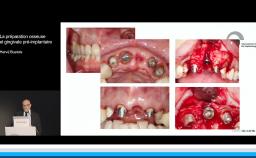

Cette présentation s’intéresse à l’influence des étapes chirurgicales sur le résultat esthétique en implantologie.

Il est communément admis qu’une épaisseur minimale de gencive kératinisée autour des implants est favorable au résultat esthétique mais aussi au maintien d’une bonne santé des tissus péri-implantaires au long terme, mais il n’existe pas de consensus à ce niveau. Une épaisseur osseuse de 2 mm autour des implants est nécessaire pour prévenir les résorptions osseuses et pour soutenir de façon pérenne les tissus mous.

• d’identifier les situations où une étape d’augmentation des tissus mous et/ou des tissus durs est nécessaire avant la mise en place de l’implant pour obtenir un résultat esthétique pérenne